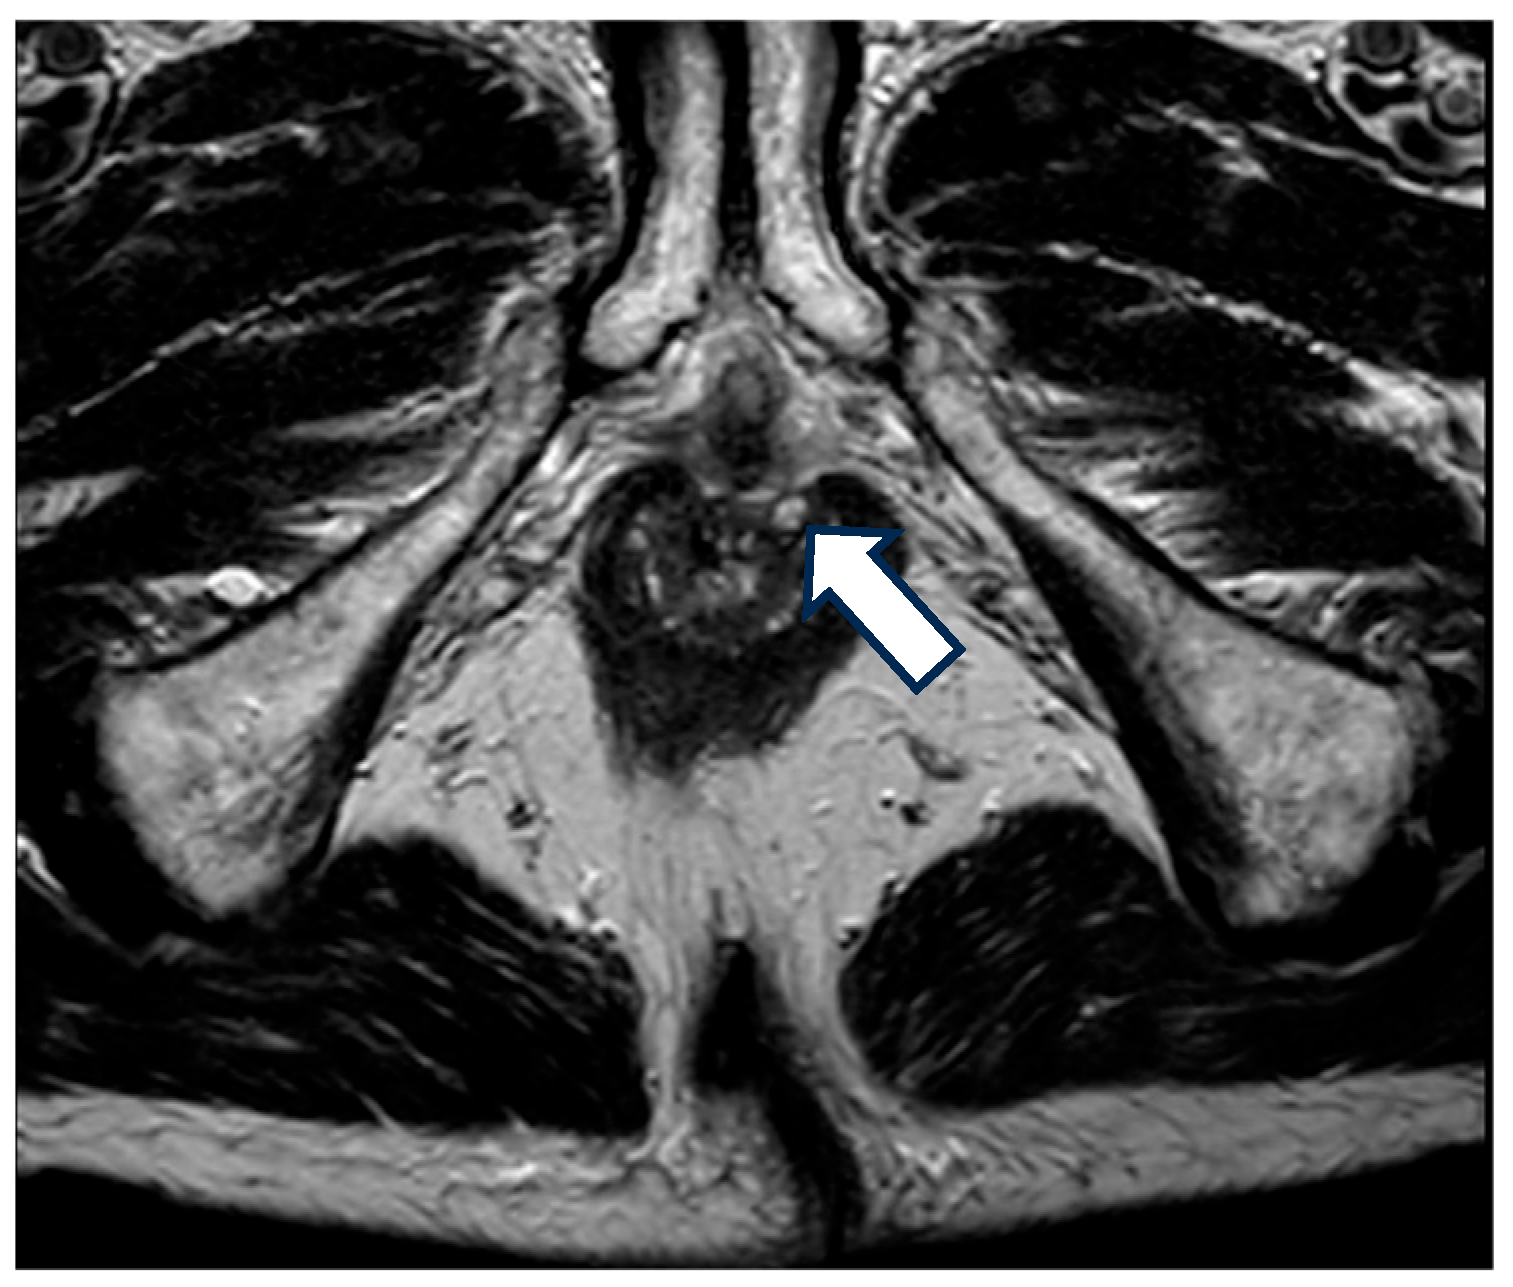

4. Classification

5. Diagnosis

| MRI | Magnetic resonance |